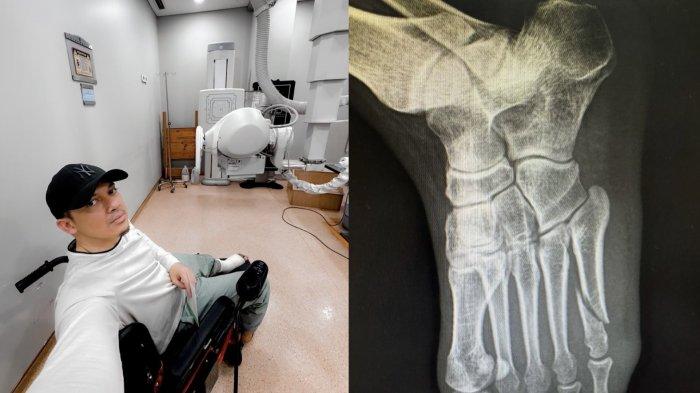

Kaki yang dibalut perban itu dinaikan Irwansyah ke kaki sebelah kanan sebagai penopang.

Rupanya Irwansyah baru saja mengalami insiden yang menyebabkan pergelangan kakinya patah.

Alhasil ia pun hanya bisa duduk di kursi roda atau berjalan menggunakan bantuan tongkat.

Lantaran kondisinya tersebut pula Irwansyah hanya bisa berdiam diri di rumah untuk sementara waktu.